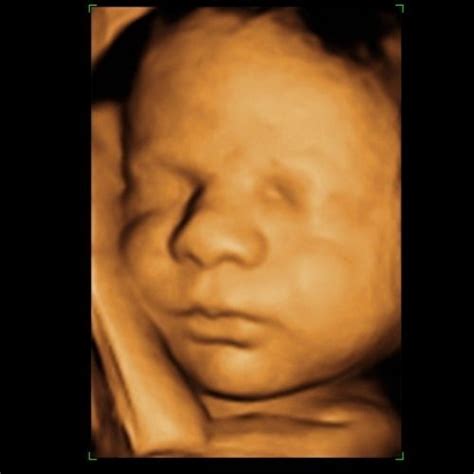

A Babamozival kiegészített terhességi ultrahangvizsgálat felejthetetlen élményt jelent a kismama számára, hisz bepillanthat kisbabája világába, akár 3D szemüveggel.

A terhesség 3. trimeszterében is számos laborvizsgálat vár ránk, többek között cukorterhelés vizsgálat és toxoplazma szűrés, de ekkor kerülhet sor a Babamozira is, mikor beleshetünk kisbabánk világába.